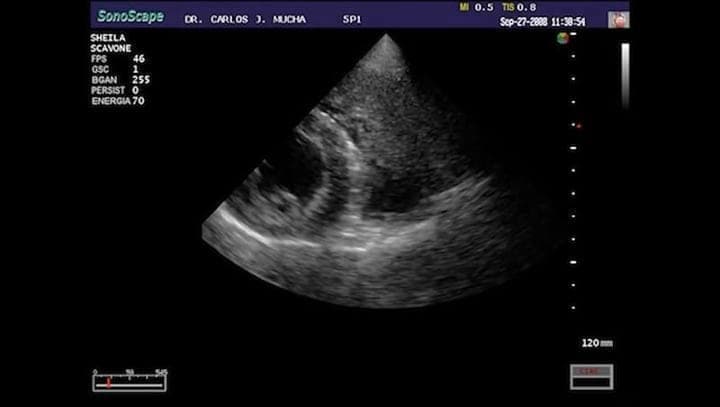

Arritmia en un canino , bloqueo auriculoventricular de tercer grado. *El vídeo fue originalmente publicado en el sitio Cardiologia Veterinaria: www.cardiologiaveterinaria.com

El video que muestran no se trata exactamente de una arritmia, es un bloqueo auriculoventricular de 3º grado con escape ventricular